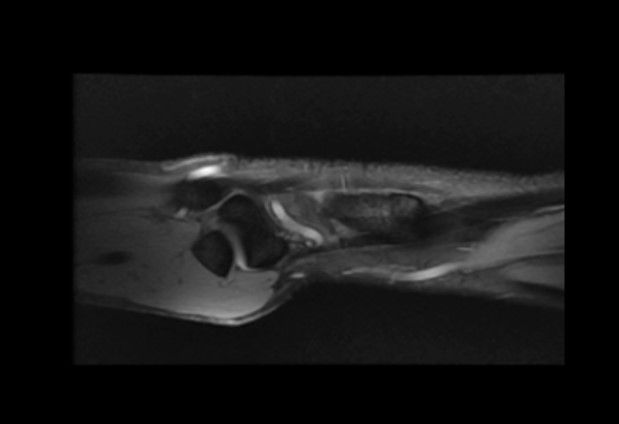

Case 20 - TFCC Rupture

38 yr, male, sweeper, right hand dominant

Right wrist pain for seven months ago

Repetative work-related trauma history in right wrist